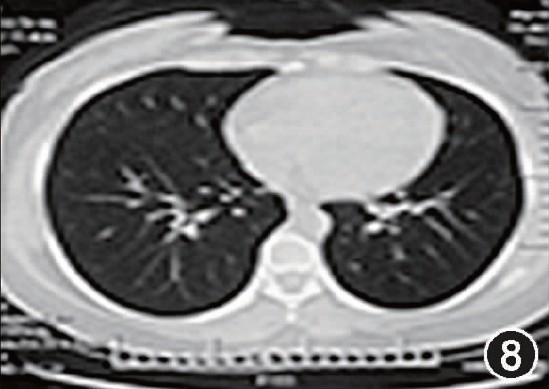

肺部阴影通常是指在透视中发现肺实质内有高密度区,在胸片上或CT上常表现为肿块或结节,一般肿块的标准是直径在4cm以上,而结节通常是指直径在